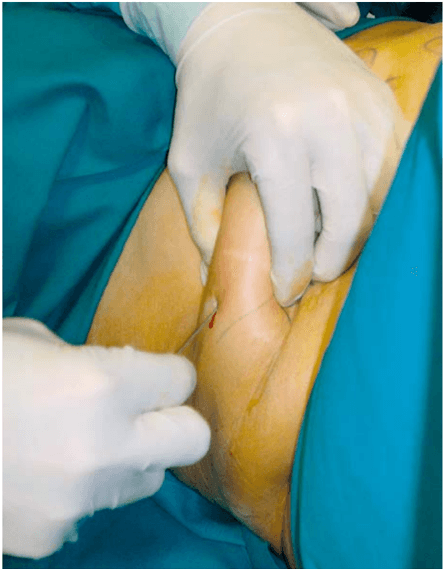

Micro-fragmented adipose tissue injection for the treatment of complex anal fistula: a pilot study accessing safety and feasibility

G. Naldini, A. Sturiale, B. Fabiani, I. Giani, C. Menconi, Techniques in Coloproctology, 2018

Intersphincteric anal lipofilling with micro-fragmented fat tissue for the treatment of faecal incontinence: preliminary results of three patients

Giovanni Cestaro, Michele De Rosa, Salvatore Massa, Bruno Amato, Maurizio Gentile, Videosurgery and Other Miniinvasive Techniques, 2015